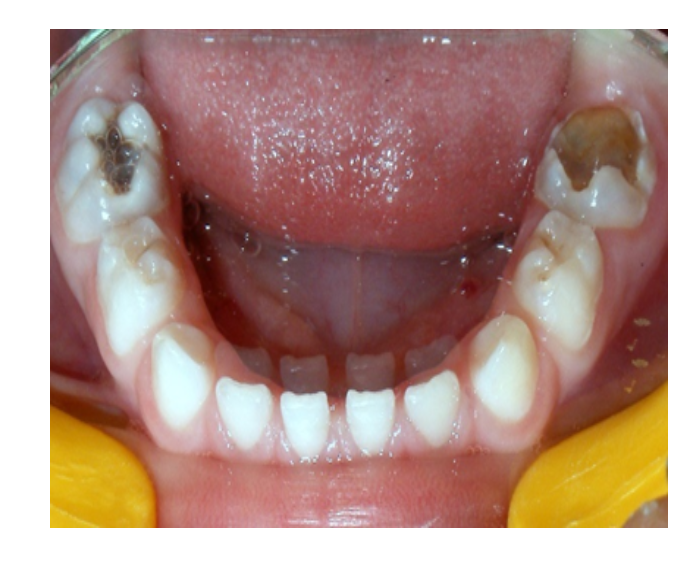

Odontología

infantil